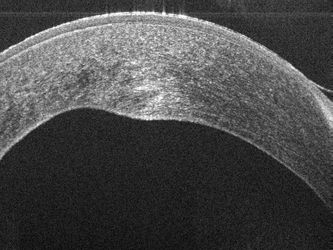

Bioptigen Inc. - сертифицированная ISO 13485 компания по производству медицинского оборудования, которая разрабатывает инновационные решения для офтальмологической визуализации. Системы класса R от компании Bioptigen Envisu (tm) идеально подходят для неинвазивной офтальмологической визуализации животных, от рыбок данио до слонов. Используя маломощный свет в ближнем инфракрасном диапазоне, Envisu в реальном времени генерирует объемные изображения микроструктуры глаза с высоким разрешением от роговицы до сетчатки в реальном времени. Компания Bioptigen получила одобрение CE на продажу своих портативных систем Envisu R2000 для доклинического использования и систем C2000 для клинического использования в ЕС.